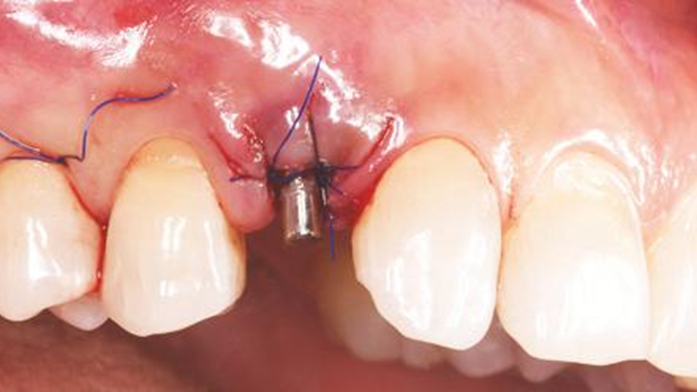

Clinical case: Immediate placement in maxillary anterior narrow space using Advanced Intermezzo

- Courtesy of Dr. Jung Sam Lee, Korea -

Advanced Intermezzo. anterior esthetics, esthetic, provisional restoration, esthetic zone, #13, maxillary anterior, Dr. Jung Sam Lee, anterior aesthetics, aesthetic, aesthetics

Advanced Intermezzo implant system